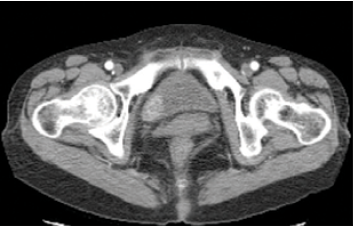

방광암이 있는 경우, 주변 조직으로의 침윤 정도 및 림프절, 다른 장기로의 전이 여부, 신우 및 요관의 종양 동반 여부 등을 확인하기 위하여 전산화단층촬영 (CT), 자기공명영상(MRI), 뼈스캔 검사 등을 시행합니다.

[사진] 방광암 환자의 CT 소견